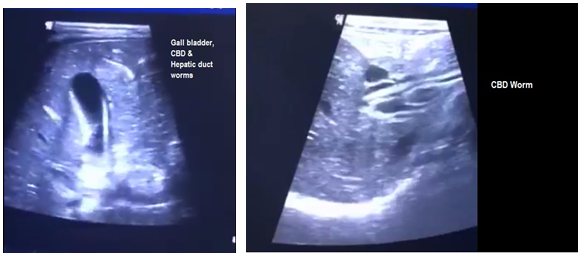

In 20 cases with biliary ascariasis observed with ultrasonography, there were 8 patients with gallbladder (Figure 1-2) and 7 with worms in the common bile duct (Figure 3-4). In 5 cases, the worms were found in the main hepatic duct (Figure 5-6) and pancreatic duct (Figure 7-8) and no case was seen with complicated intrahepatic abscess cavity. Ultrasound confirmed the dilatation in common bile duct as estimated about 10-20 mm, in 7 patients (Table 1 and Pie chart 1).

Figures 3-4 Common bile duct worm.

Figures 5-6 Haptic duct worm.